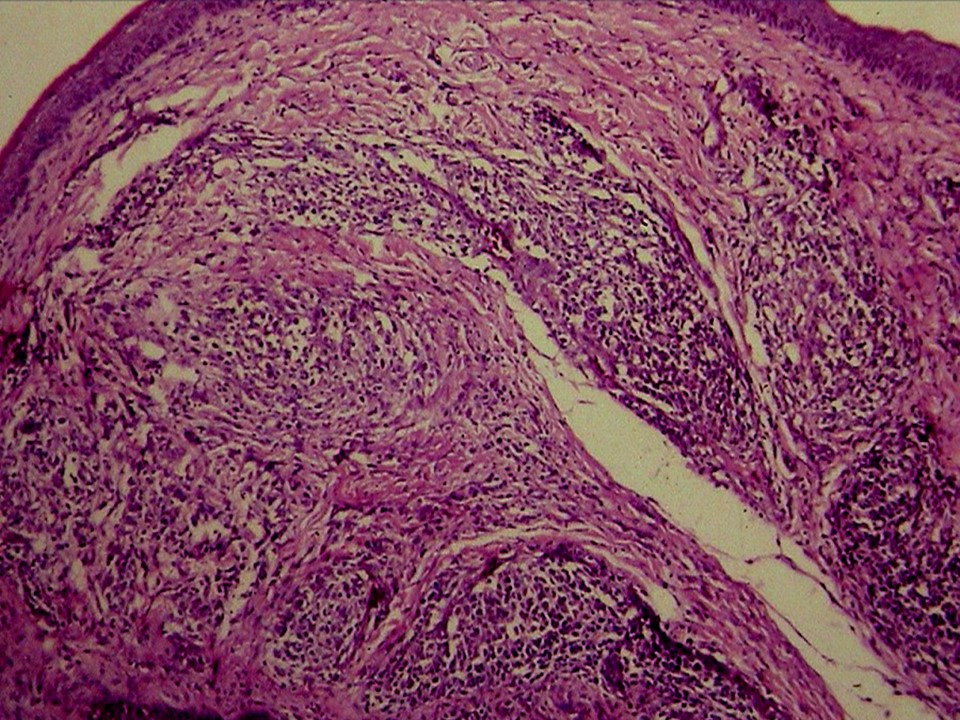

疾病中文名稱:馬立克病

疾病英文名稱:Marek's disease

影像說明:翼神經受侵犯而翅膀下垂,坐骨神經受侵犯呈劈腿狀